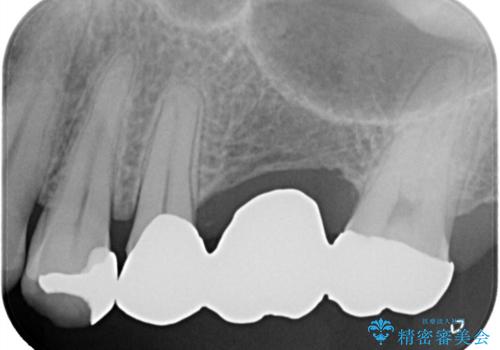

左上に保険適用の⑤ 6 ⑦ブリッジが入っており、7番目の歯と被せものとの境目に段差があり、そこに汚れが停滞したいたため適合の良いオールセラミッククラウンブリッジでのやり替えとなりました。

左上7番遠心マージン不適を認め、そこに汚れが停滞していたためやり替えをおすすめし、汚れが付着しずらく審美性に優れたセラミッククラウンブリッジでのやり替えとなりました。